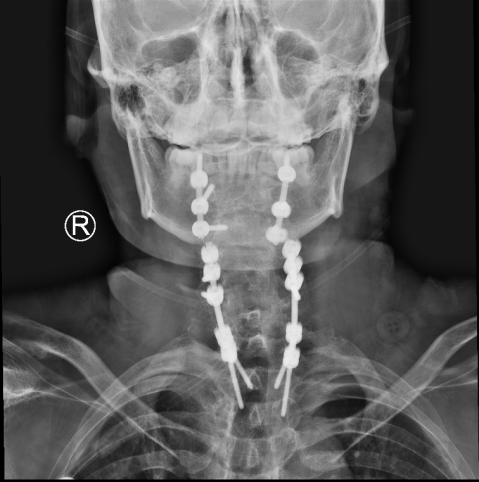

金先生伤后第7天,姜主任医师团队在麻醉手术科的密切配合下成功为他实施手术。姜主任凭借多年徒手置钉的过硬技术经验,2小时不到便完成了手术,术中出血仅100ml。术后CT显示齿状突完美复位,螺钉“不偏不倚”的位置恰到好处。术后,金先生在骨科护士长张霞芬护理团队的精心护理下,15天后伤口拆线康复出院。

第一步是先从颈椎后方入路,使用手术器械将骨折脱位复位,然后用螺钉固定;第二步是待患者恢复一段时间后再行前路手术。这个术式的难点在于强直性脊柱炎患者有严重的骨质增生表现,解剖标志不清,置钉有难度;其次,CT显示后方关节突交锁,复位困难。姜主任再次凭借多年手术经验,在二代0臂机的保驾护航下,成功地将螺钉置入椎体内,手术历经3小时。术后,金先生的右侧肢体偏瘫有了明显改善,2周后出院。

一个月后,金先生迎来了他的第二步的手术:颈前路植骨融合固定术。手术很顺利,1周后,金先生出院。出院前金先生的妻子王女士眼含热泪跟床位护士袒露心声:“我们很信赖姜主任和独墅湖医院骨科,是独墅湖医院给了我家先生两次生的机会。我们全家衷心感谢你们!”金先生也诚挚地向姜为民主任表达了自己的感激和敬意。王女士紧紧拉住前来探望的张霞芬护士长的手说道:“感谢姜主任救了我老公,拯救了我们这个家庭,感谢骨科全体医护人员对我们的照顾……”